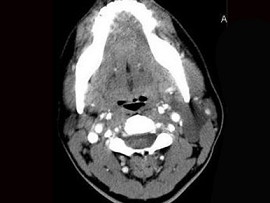

8.患者腫塊圖像及影像學檢查結果見下圖,本患者應考慮為  (    )